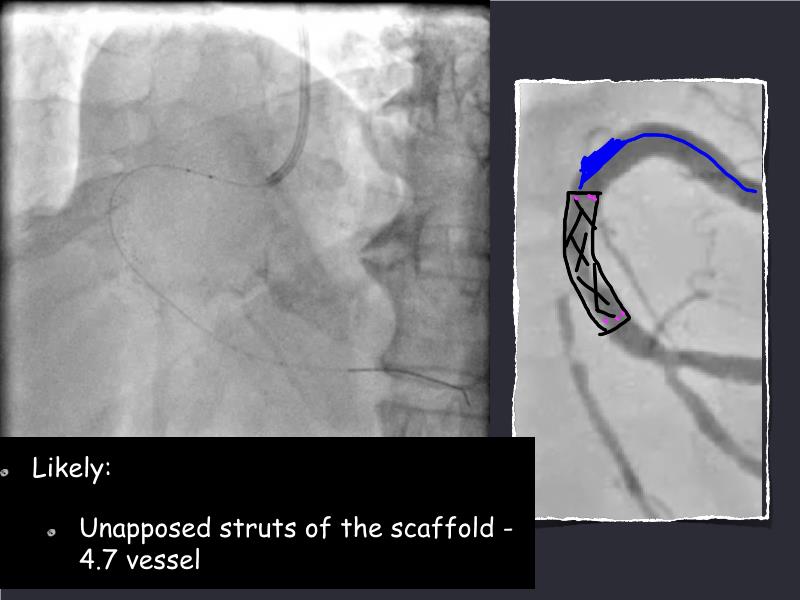

- To understand novel tools and techniques for effective management of bifurcation lesions and long diffused lesions using dedicated stenting solutions